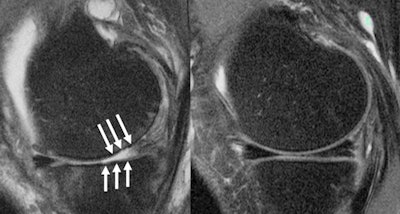

The team found significant ties between corticosteroid injection and postinjection progression of whole-organ MRI scores over two years for the knee overall, lateral meniscus, lateral cartilage, and medial cartilage.

However, the study authors found no such links between either injection type and pain progression, as well as progression of MRI scores over the two years prior to injection.